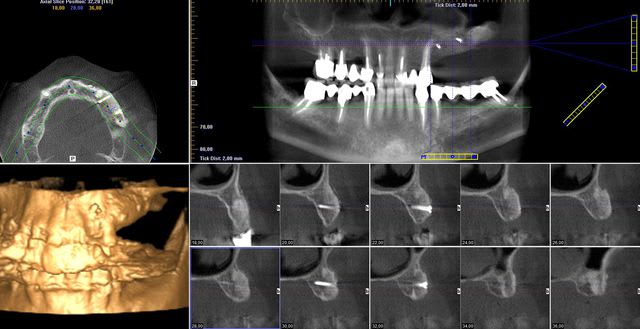

On est en 13 14 15, patiente d'une soixantaine d'années, sans antécédents médicaux ni dentaires. Un peu frileuse pour les grosses chirs mais elle était néanmoins partante pour les implants.

il semble y avoir une belle perte en hauteur aussi en distal de 12 sur la pano mais qu'on voit moins sur les coupes.

Pour moi c'est greffe onlay, mais j'aimerais bien voir exactement les coupes juste en distal de 12.

Ancien site d'extraction, la pano est vieille.

Ce sont les dernières coupes qui correspondent au site de la 13